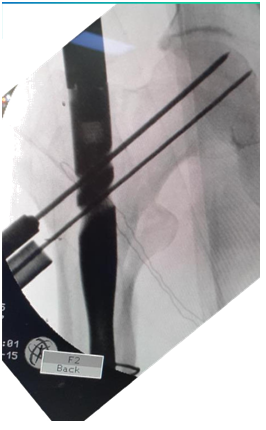

Indications (Figure 1)

1. Unstable IT fractures

1. Comminuted

2. Reverse oblique

3. Subtrochanteric extension

2. Associated shaft fracture

Figure 1 PFN in IT fractures.